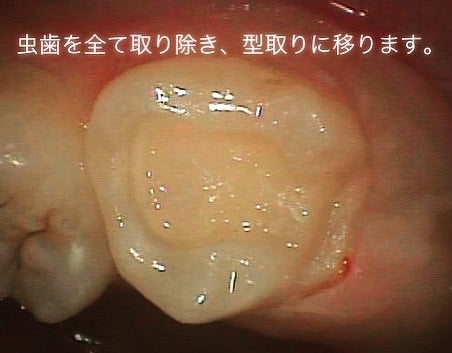

<虫歯を取りきりセラミックを被せる形に形成した状態>

<虫歯を取り除いた状態>

▶︎先程と同様に虫歯を取りきり、セラミックの形を整え、型取りを行います。